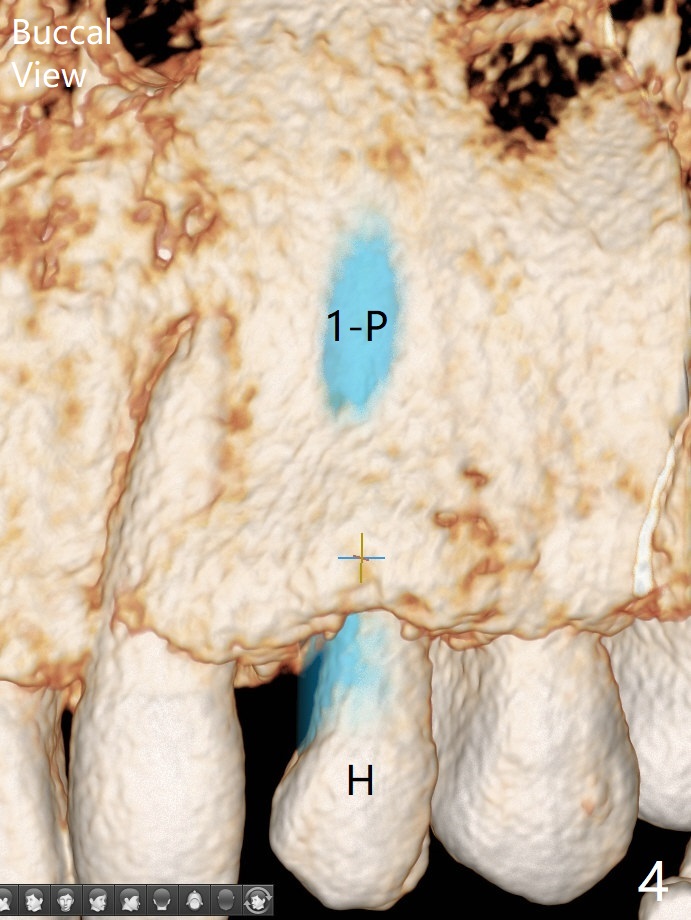

Since there is limited vertical and horizontal (buccopalatal) space at H, it appears that 1-piece implant may offer simple treatment to avoid angled abutment (Fig.1). Because of the thin concave buccal plate over the narrow implant (Fig.2,3,4 *), a remote incision will be made immediately post implantation (Fig.5 red line). After subperiosteal dissection, bone graft will be deposited to avoid implant thread exposure and restore the canine prominence (Fig.6,7). Prepare PRF for sticky bone. Take preop photo to show buccal apical concavity.